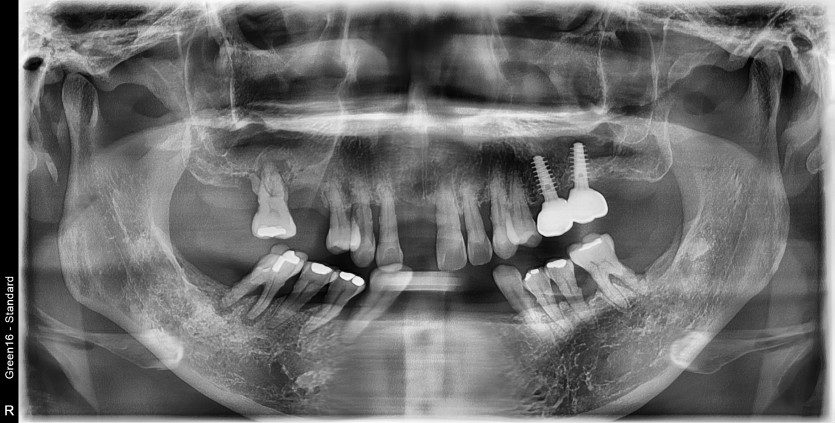

만 56세 상 하악 임플란트 증례

상 하악 임플란트 증례입니다.

12개의 임플란트로 완성하였습니다.

(상악 6개, 하악 6개)